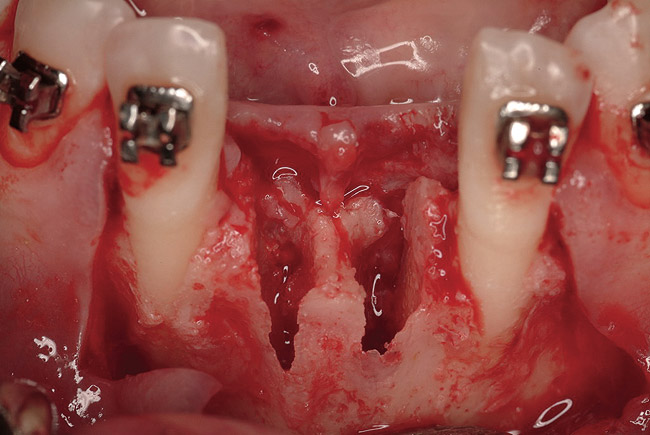

Figure 16  The edentulous anterior sextant. Portions of the facial bony wall remain in the maxillary left central and lateral incisor region. The long-standing abscess associated with tooth Nos. 7 and 8 has resulted in total loss of the bony plate in this area.

Figure 16